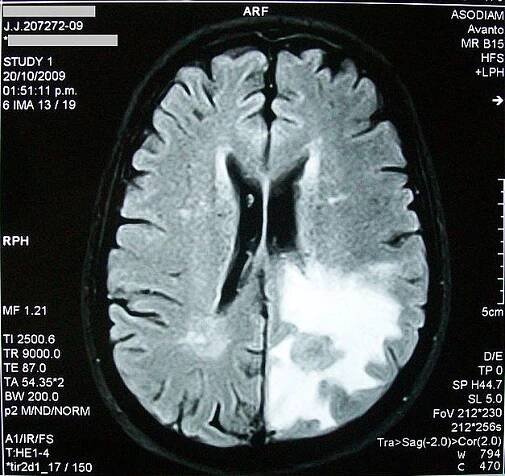

MRI THE BRAIN.Středně pravidelný vazogenní edém s posunem o 0,7 cm na levou stranu.. — Stock obrázek

Edém mozku je obvykle rozdělován do dvou typů: vazogenní a cytotoxický. Rozvoj vazogenního edému mozku je spojen s poškozením hematoencefalické bariéry.